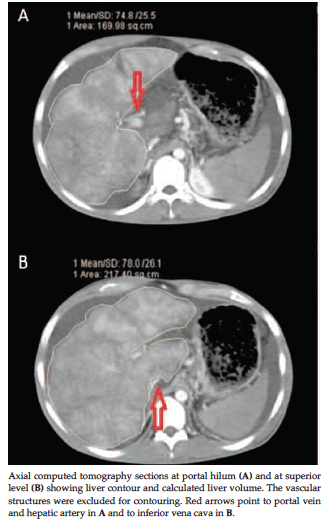

At an interactive workstation (Leonardo, Siemens) for each slice of a 10-mm reconstruction interval image, the liver contour was delineated manually using the optical mouse. The extrahepatic vena cava and portal vein, the gallbladder, and attached ligaments were excluded (Figure 1). Volumes were calculated by summation of the slice volumes. The density of a healthy liver was previously10 found to be 1 kg/L; however, according to Goumard and associates,11 the density of cirrhotic liver parenchyma can be considered to be 1.1 kg/L. Therefore, for our study, the estimated cirrhotic liver weight (CLW) was the result of multiplying the summation of the slice volumes by 1.1. Explanted cirrhotic livers were weighed immediately by pathology staff.